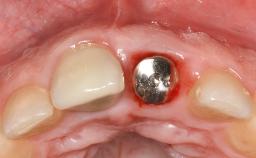

Ridge Preservation and Implant Placement for a Fixed Dental Prosthesis After a Car Accident

It is well known to clinicians that any removal of teeth will, over time, cause the dimensions of the alveolar ridge to be reduced by resorption of the bundle bone and by changes related to external modeling. This development is particularly evident in the crestal region with its thin buccal bone that consists of bundle bone almost entirely. The facial bone will rapidly resorb as blood supply from the periodontal ligament gets disrupted (Araújo and Lindhe 2005). There is no reason why traumatic tooth loss should not have the same consequences. It takes more than achieving implant osseointegration for a treatment outcome to be considered successful. No deficiency of bone or soft tissue is acceptable when an ideal esthetic outcome is the goal. Several articles (Sanz and coworkers 2011; Vignoletti and coworkers 2011) have reported on techniques of improving the alveolar ridge for implant treatment, notably focusing on protecting tissues from resorption.